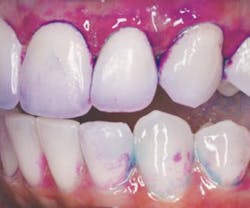

What type of disclosing agent should you use? Well, this is where a few things have changed. First of all, not all disclosing agents are solutions. GC America has a plaque-disclosing gel, called GC Tri-plaque ID, that reveals new, mature, and acid-producing biofilm. New plaque is disclosed as pink, mature is purple, and acid-producing biofilm is a light blue as seen in Figure 1. An interesting study examined the clinical benefit of this three-way disclosing agent in conjunction with caries risk assessments for children. The study revealed a correlation between an increase in purple and blue dye on the teeth and an increase in carious lesions.1

Figure 1: Tri-Plaque ID discloses acidic biofilm light blue. Photo courtesy of Pamela Maragliano-Muniz, BSDH, DMD.